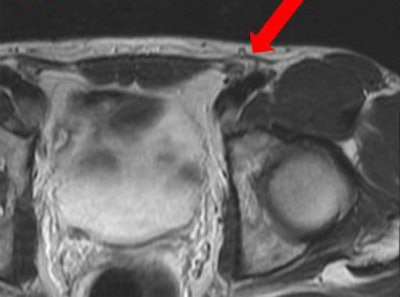

Inguinal hernias, whether occult or obvious, and lipomas of the spermatic cord or round ligament are important etiologies to consider in the diagnosis of groin pain. This axial T2-weighted MR image of the pelvis shows a spermatic cord lipoma.

Inguinal hernias, whether occult or obvious, and lipomas of the spermatic cord or round ligament are important etiologies to consider in the diagnosis of groin pain. This axial T2-weighted MR image of the pelvis shows a spermatic cord lipoma.Tendon injuries are often overuse injuries or a result of a single traumatic event, they continued. Athletic muscle injuries present as a heterogeneous group of muscle disorders. The most widely used classification is an MRI-based graduation defining four grades: grade 0 with no pathological findings, grade 1 with a muscle edema only but without tissue damage, grade 2 as partial muscle tear, and grade 3 with a complete muscle tear.

Inguinal hernias, whether occult or obvious, and lipomas of the spermatic cord or round ligament are important etiologies to consider in the diagnosis of groin pain, the authors wrote. Many patients do not complain of a bulge, but instead complain chiefly of groin pain, unaware of the vast differential diagnosis list involved.

These hernias are often diagnosed with history and physical exam alone, and treated accordingly. An occult hernia can be a cord lipoma or indirect hernia sac that tracks along the spermatic cord within the inguinal canal creating compression on the ilioinguinal or genitofemoral nerves, they added. Lipomas of the cord and round ligament cause similar pain to that of a hernia.